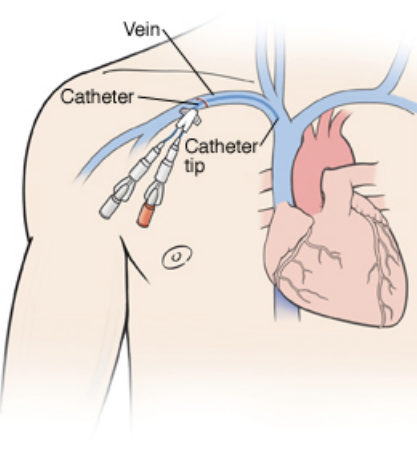

Common Procedures Performed in the Neurosciences ICU

Arterial Line (click here)